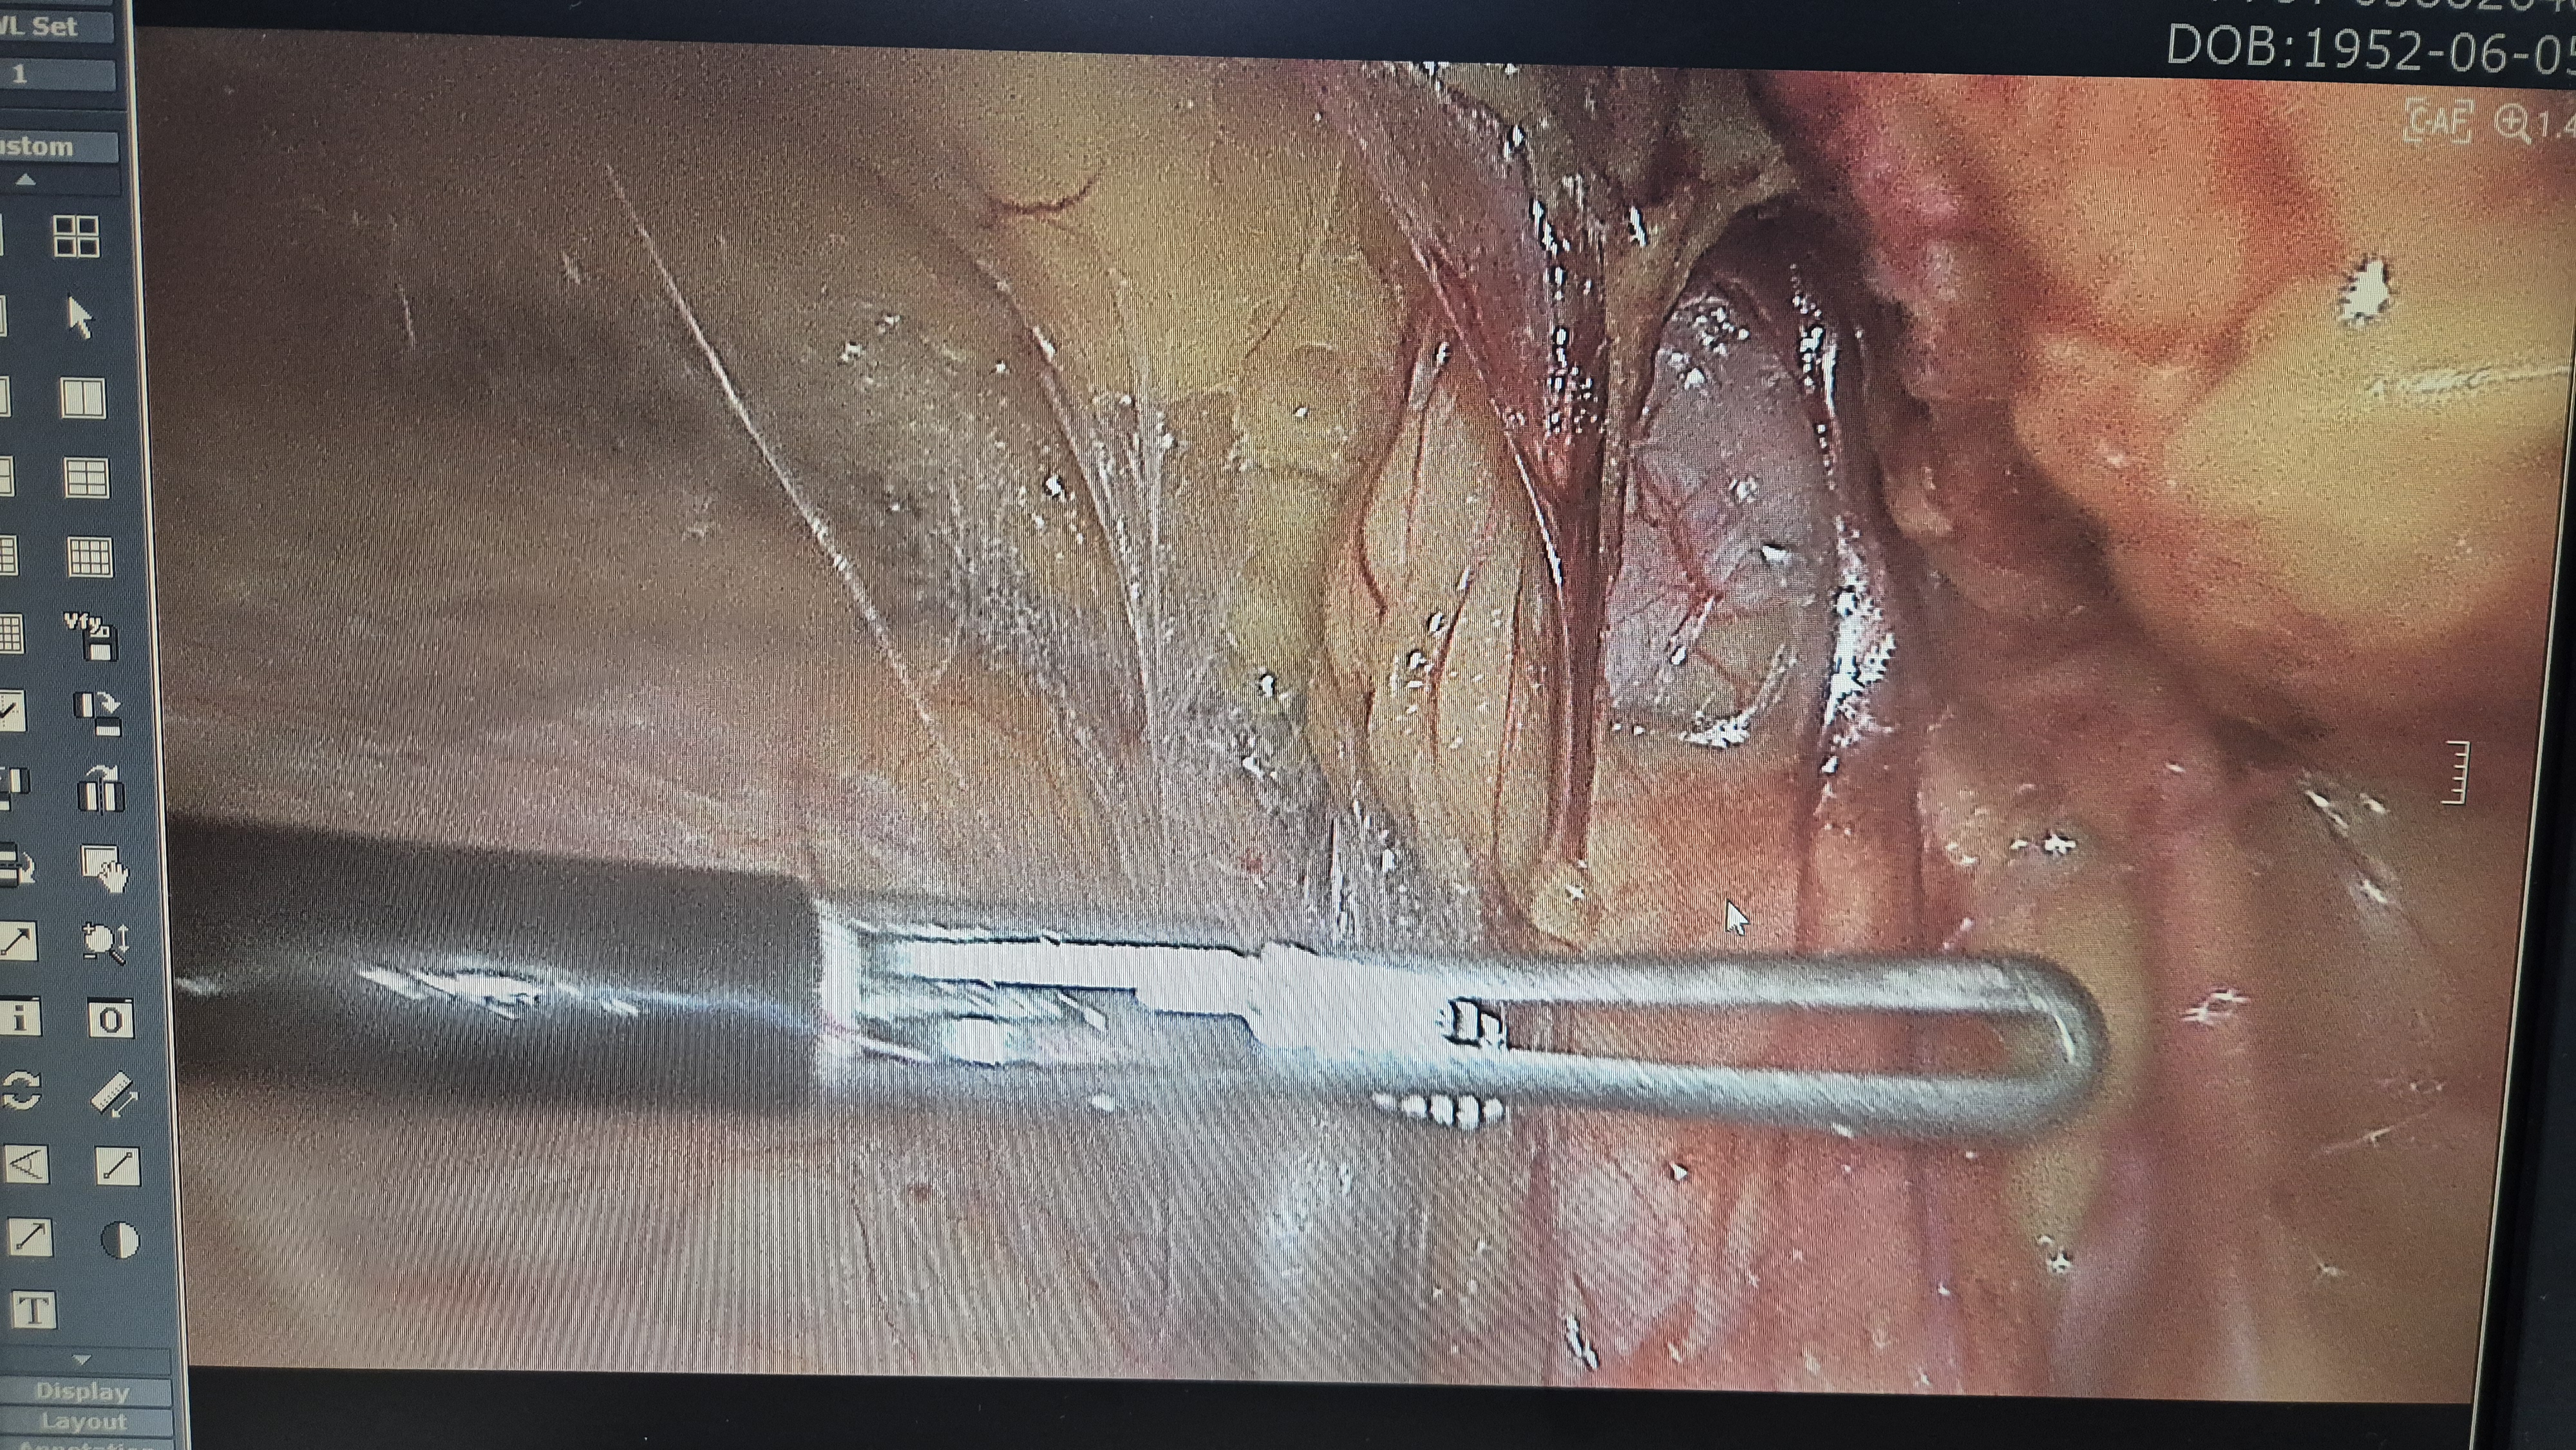

좌측 직접 탈장.

메쉬로 보강.